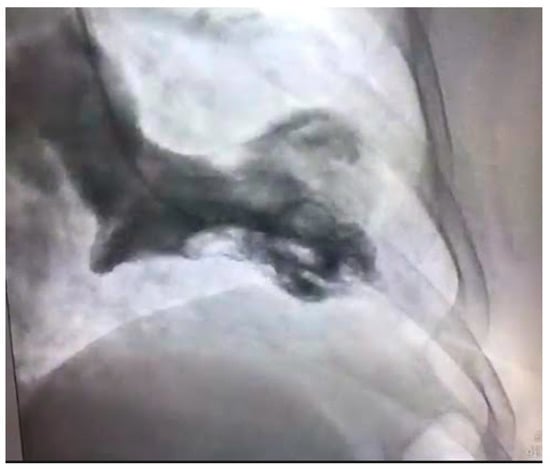

Figure 2.

Severe atherosclerotic stenosis of the LAD in a female patient with ACS.